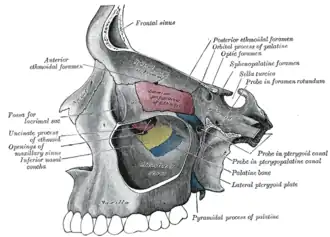

Openings

There are two important foramina, or windows, two important fissures, or grooves, and one canal surrounding the globe in the orbit. There is a supraorbital foramen, an infraorbital foramen, a superior orbital fissure, an inferior orbital fissure and the optic canal, each of which contains structures that are crucial to normal eye functioning. The supraorbital foramen contains the supraorbital nerve, the first division of the trigeminal nerve or V1 and lies just lateral to the frontal sinus. The infraorbital foramen contains the second division of the trigeminal nerve, the infraorbital nerve or V2, and sits on the anterior wall of the maxillary sinus. Both foramina are crucial as potential pathways for cancer and infections of the orbit to spread into the brain or other deep facial structures.

The optic canal contains the (cranial nerve II) and the ophthalmic artery, and sits at the junction of the sphenoid sinus with the ethmoid air cells, superomedial and posterior to structures at the orbital apex. It provides a pathway between the orbital contents and the middle cranial fossa. The superior orbital fissure lies just lateral and inferior to the optic canal, and is formed at the junction of the lesser and greater wing of the sphenoid bone. It is a major pathway for intracranial communication, containing cranial nerves III, IV, VI which control eye movement via the extraocular muscles, and the ophthalmic branches of cranial nerve V, or V1. The second division of the trigeminal nerve enters the skull base at the foramen rotundum, or V2. The inferior orbital fissure lies inferior and lateral to the ocular globe at the lateral wall of the maxillary sinus. It is not as important in function, though it does contain a few branches of the maxillary nerve and the infraorbital artery and vein.[7] Other minor structures in the orbit include the anterior and posterior ethmoidal foramen and zygomatic orbital foramen.

Bony walls

yellow = frontal bone

green = lacrimal bone

brown = ethmoid bone

blue = zygomatic bone

purple = maxillary bone

aqua = palatine bone

red = sphenoid bone

teal = nasal bone (illustrated but not part of the orbit)

The bony walls of the orbital canal in humans do not derive from a single bone, but a mosaic of seven embryologically distinct structures: the zygomatic bone laterally, the sphenoid bone, with its lesser wing forming the optic canal and its greater wing forming the lateral posterior portion of the bony orbital process, the maxillary bone inferiorly and medially which, along with the lacrimal and ethmoid bones, forms the medial wall of the orbital canal. The ethmoid air cells are extremely thin, and form a structure known as the lamina papyracea, the most delicate bony structure in the skull, and one of the most commonly fractured bones in orbital trauma. The lacrimal bone also contains the nasolacrimal duct. The superior bony margin of the orbital rim, otherwise known as the orbital process, is formed by the frontal bone.[8]

Medial wall of left orbit

Medial wall of left orbit -